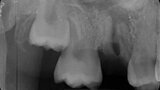

Fig. 19a: Radiographs: Pre-op periapical.